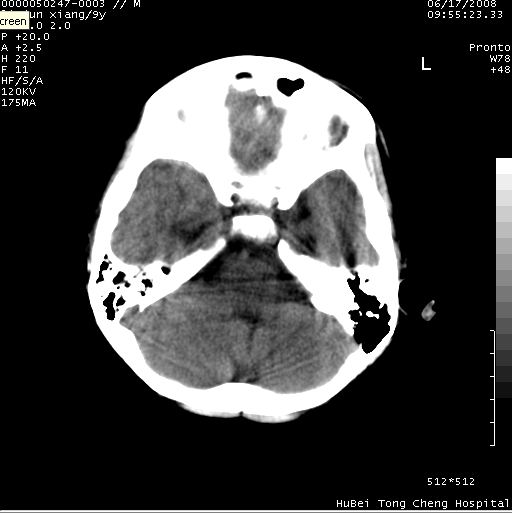

患儿 男,9岁。既往有“脑积水,脑萎缩?”病史(无影像检查资料),现无明显不适。其家长要求ct检查。

颅脑ct轴位平扫(层厚、层距均为10mm),图像如下:

考虑为先天变异。

支持变异。